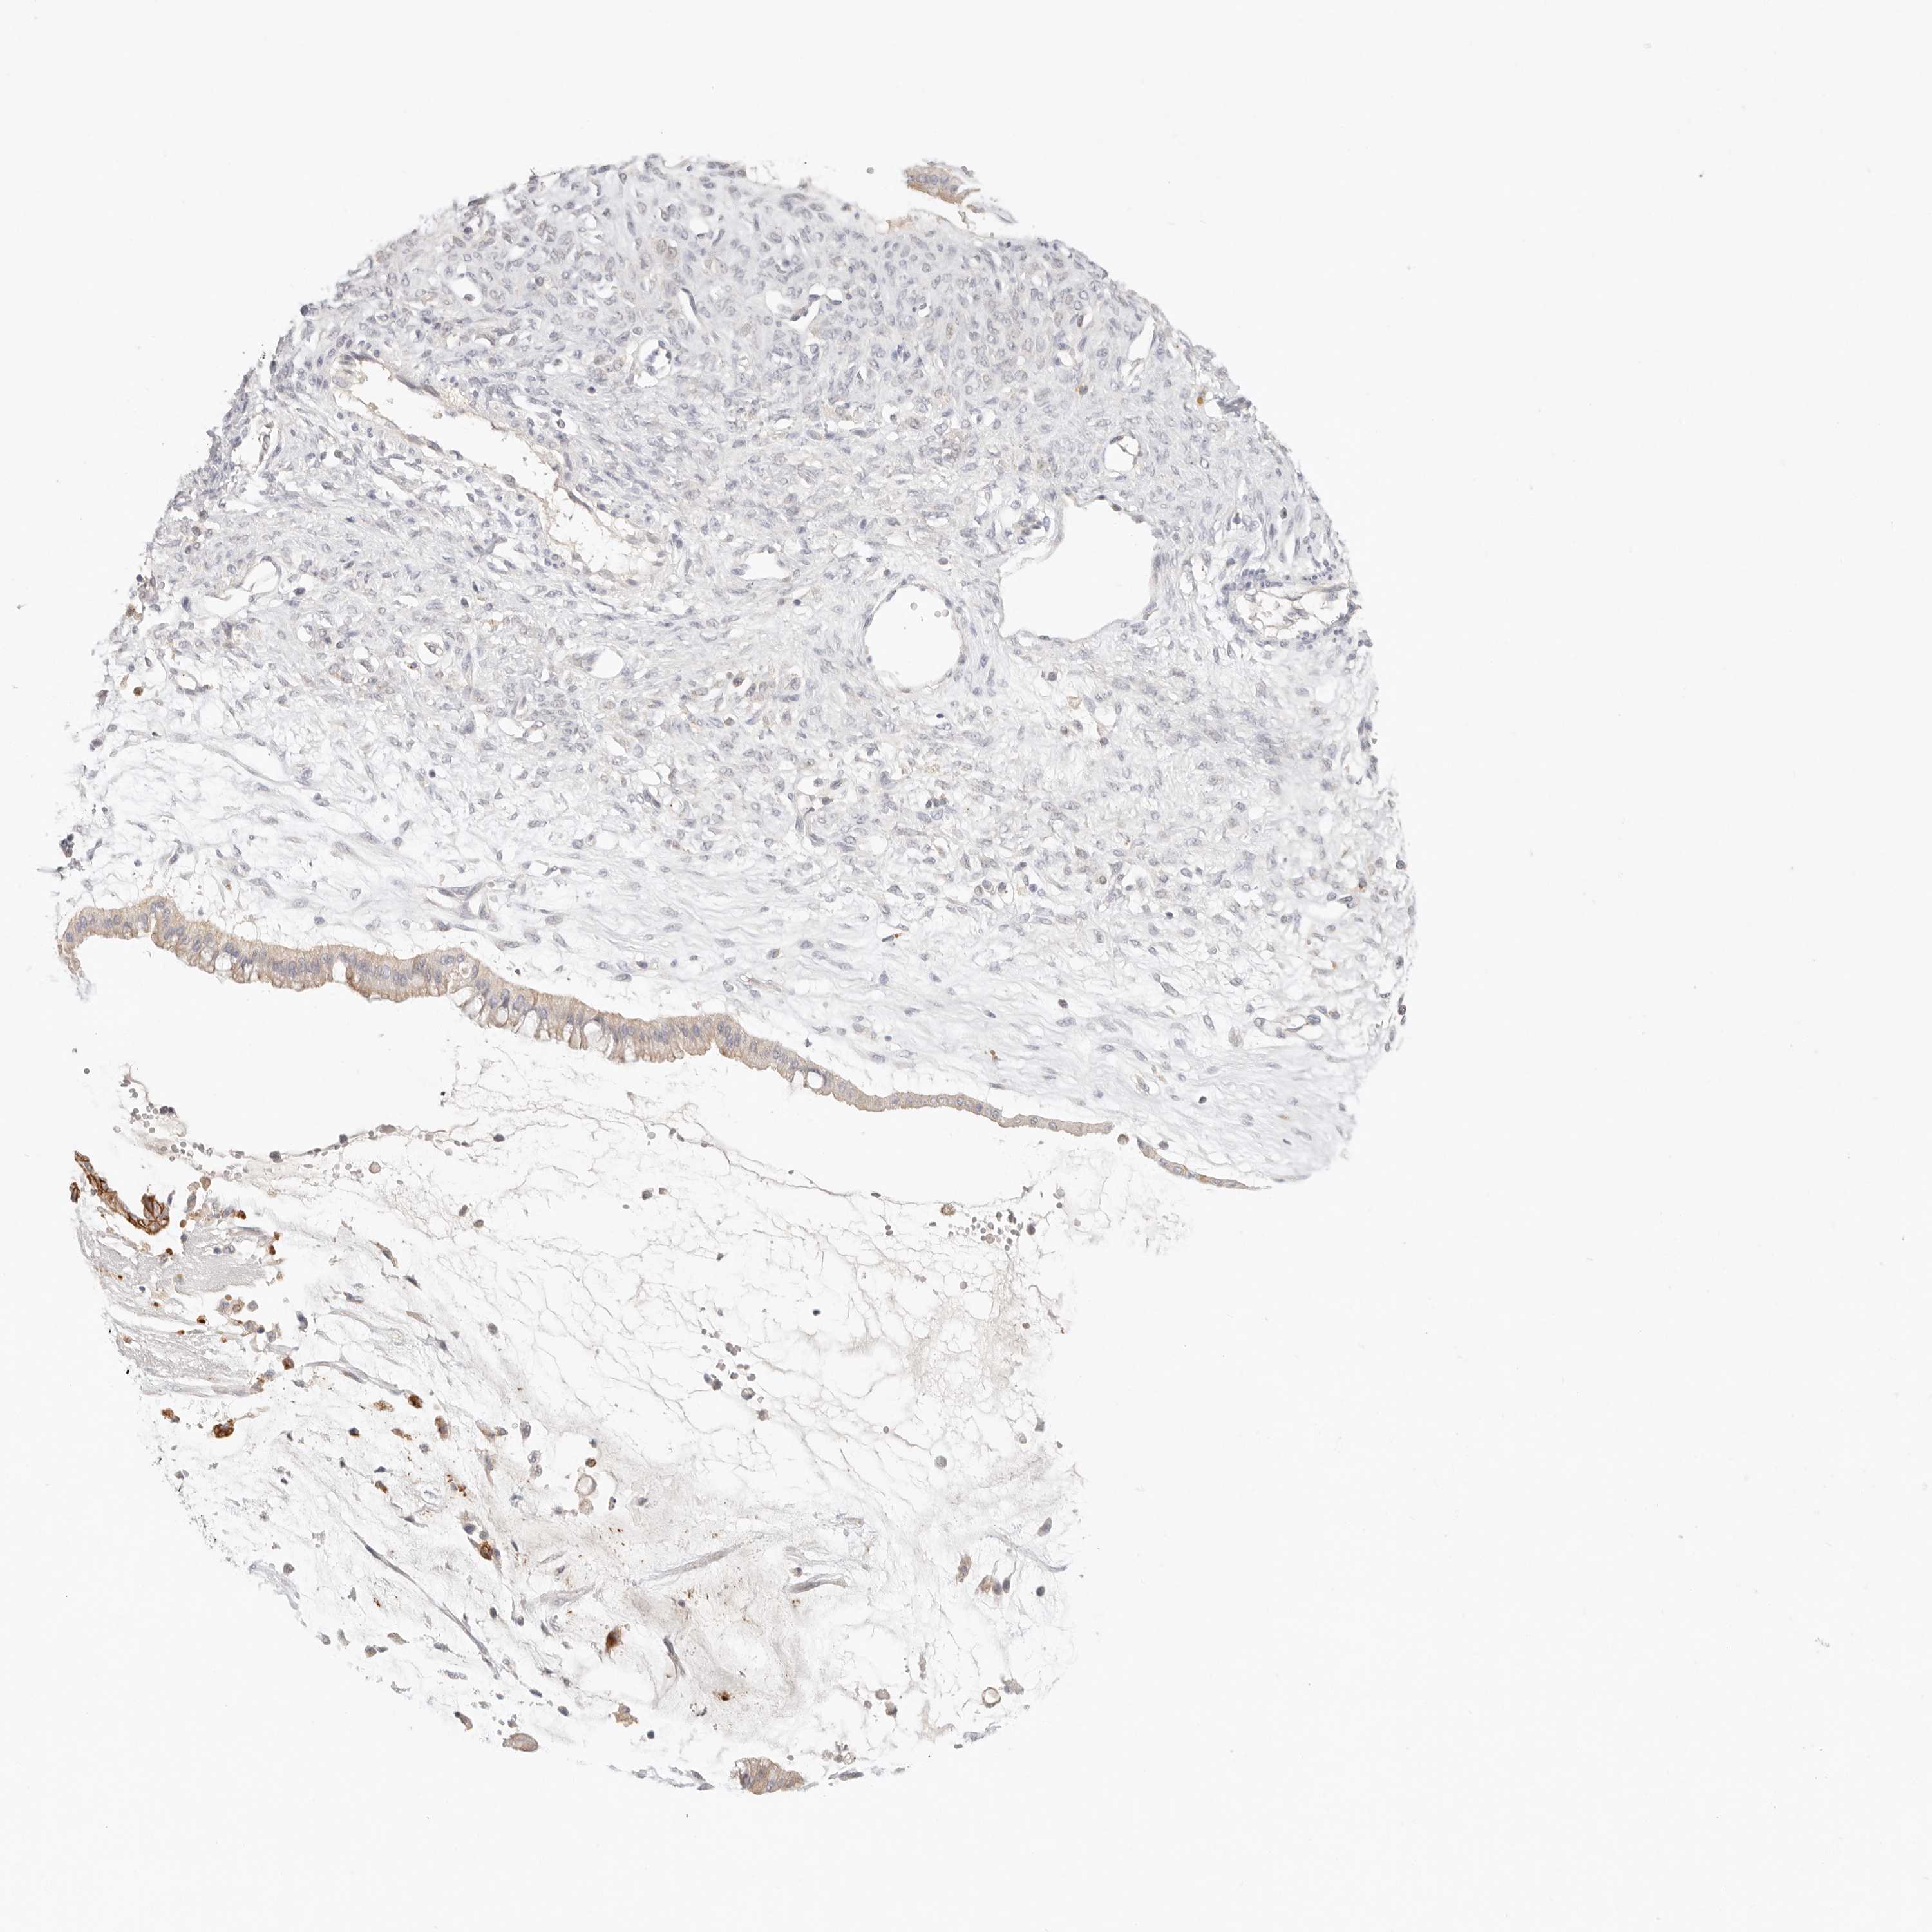

OVARIAN CANCER - Protein expressioni

A mouse-over function shows sample information and annotation data. Click on an image to view it in a full screen mode. Samples can be filtered based on level of antibody staining by selecting one or several of the following categories: high, medium, low and not detected. The assay and annotation is described here.

Note that samples used for immunohistochemistry by the Human Protein Atlas do not correspond to samples in the TCGA dataset.

Antibody stainingi

Antibody staining in the annotated cell types in the current human tissue is reported as not detected, low, medium, or high, based on conventional immunohistochemistry profiling in selected tissues. This score is based on the combination of the staining intensity and fraction of stained cells.

Each image is clickable and will lead to virtual microscopy that enables deeper exploration of all samples and also displays staining intensity scores, fraction scores and subcellular localization as well as patient and tissue information for each sample.

Antibody HPA028823

Antibody HPA051556

Cystadenocarcinoma, serous, NOS

Carcinoma, endometroid

Cystadenocarcinoma, mucinous, NOS

Carcinoma, NOS